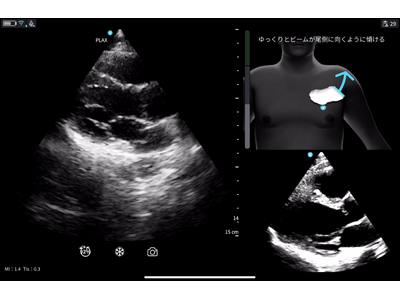

※Cardiac Guidance/ Interpretationの実際の画面

※Cardiac Guidanceによる心エコー検査のリアルタイムガイド表示機能。Quality Meterで画像クオリティを確認、画面上部にはイラストとともに「時計回りにゆっくりと回転」などリアルタイムに様々なガイダンスが表示されます。

「Vscan Air SL Ally」には、心エコー検査をサポートする Cardiac Guidance機能とCardiac Interpretation機能が備わっています。Cardiac Guidanceは、検査手技をAIがリアルタイムでガイドしながら、画像の品質を担保し、一方のCardiac Interpretationは、取得した画像をAIが解析し、診断精度を引き上げます。

リアルタイムで操作者をサポートするガイド機能で、プローブ(探触子)の位置、角度、肋間操作、深度を画面上で指示し、より正確で高品質な画像取得をサポートします。さらに、画像品質のインジケータ機能を備えており、最適なスキャン画像が得られているか否かを判定します。また、一定レベル以上の品質を認識した際には、プローブを一定時間保持することで自動的に画像を保存します。Cardiac Guidanceの機能により、複雑な心エコー検査を簡便かつ正確に実施することが可能となり、臨床現場だけでなく、大学や基幹病院のトレーニングセンターでの教育利用にも「Vscan Air SL Ally」の導入が期待されます。